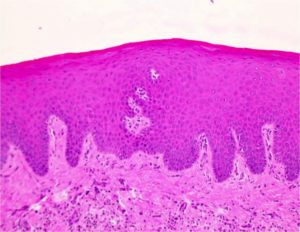

Важно! Как выглядит лейкоплакия вульвы в каждом случае, вы можете просмотреть на фото. Это поможет более точно понять отличительные признаки каждой формы заболевания по внешним признакам.

- прицельную биопсию — с подозрительных участков эпителия делаю забор небольших кусочков тканей, которые исследуются под микроскопом на патогенную микрофлору и онкоцитологические изменения;

- Биопсия тканей вульвы. Наиболее эффективная диагностическая методика, которая в 100% случаях позволяет поставить точный диагноз.

Лейкоплакия вульвы требует исключения злокачественного процесса во влагалище. Подозрительные участки лейкоплакии исследуются на наличие атипичных клеток путем биопсии и гистологического исследования.